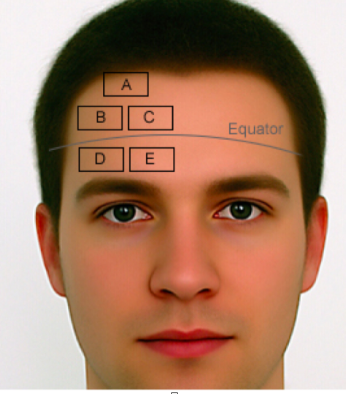

Safe zone for halo application (anterior pins)?

Lateral 1/3 of eyebrow, below the equator (site D in figure)

Avoids supraorbital and supratrochlear nerves